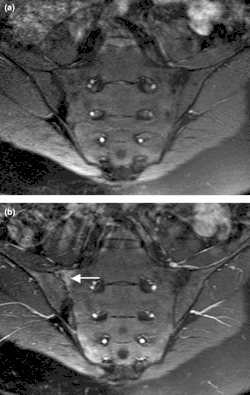

Imaging is crucial to the spondyloarthritis diagnosis process. The most distinctive radiographic observation is the sacroiliac (SI) joints' erosion, ankylosis, and sclerosis.[27] There must be clear evidence of sacroiliitis (at least grade 2 bilaterally or grade 3 unilaterally) on the radiographs to diagnose ankylosing spondylitis. When axial spondyloarthritis is suspected, sacroiliac joint radiographs are still the initial imaging approach. If radiographs clearly show sacroiliitis, then no more diagnostic imaging is required. But because structural change seen on radiographs can take months or years to emerge, normal radiographs or worrisome abnormalities only warrant additional diagnostic imaging in the context of suggestive clinical symptoms or findings.[28] Furthermore, reading sacroiliac joint radiographs can be difficult and dependent on several variables, such as the image quality, the radiological technique, the reader's background, and variations in sacroiliac anatomy.[29][30]

A challenge associated with radiographic imaging is the typical ten-year lag between the beginning of inflammatory back pain and the development of radiographic sacroiliitis.[26] MRI imaging of the spine and entheses has made it possible to distinguish between inflammatory spinal lesions associated with ankylosing spondylitis and those unrelated to it earlier than is feasible with traditional radiography. It has also allowed for accurate anatomical description of spinal components.[31] The only imaging modality that can precisely identify and evaluate spinal inflammation at this time is magnetic resonance imaging (MRI) of the sacroiliac joints and spine. It is also being developed as a gauge of disease activity and response to treatment.[5]